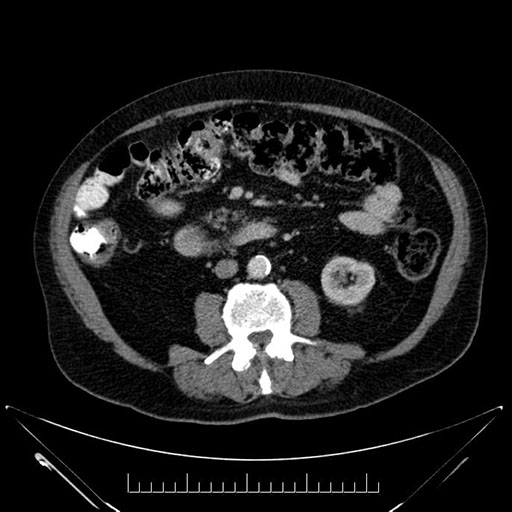

Whipple (pancreaticoduodenectomy) [case 7]

Imaging Analysis

Look through the patient's CT scan to identify any areas of concern for the necessary procedure.

Based on your CT findings, which issue(s) would give reason for "planned slowing down moment(s)" in this case?

Considering a standard Whipple procedure, what step(s) of the operation would you do differently in this case?